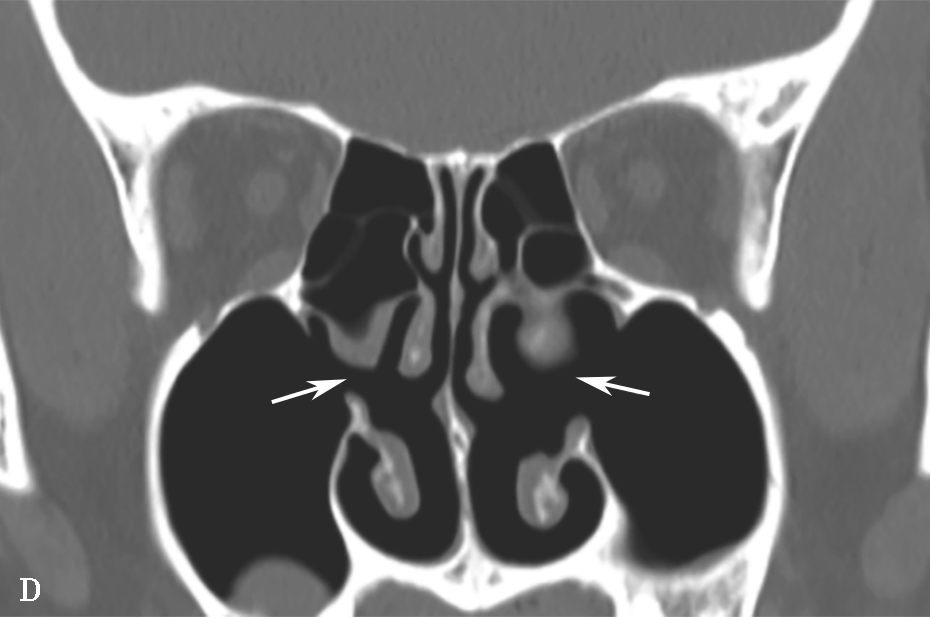

即中组筛房,位于鼻丘后,由1~3个气房构成,内下壁与筛骨钩突间形成半月裂间隙。筛泡过度气化,可能造成筛漏斗及半月裂狭窄,影响引流;过度气化至眶下壁时,称为眶下气房,又称Haller气房,也可能影响上颌窦的引流(图1-3-6)。

图1-3-6 筛泡解剖变异

A.双侧Haller气房;B.左侧筛大泡